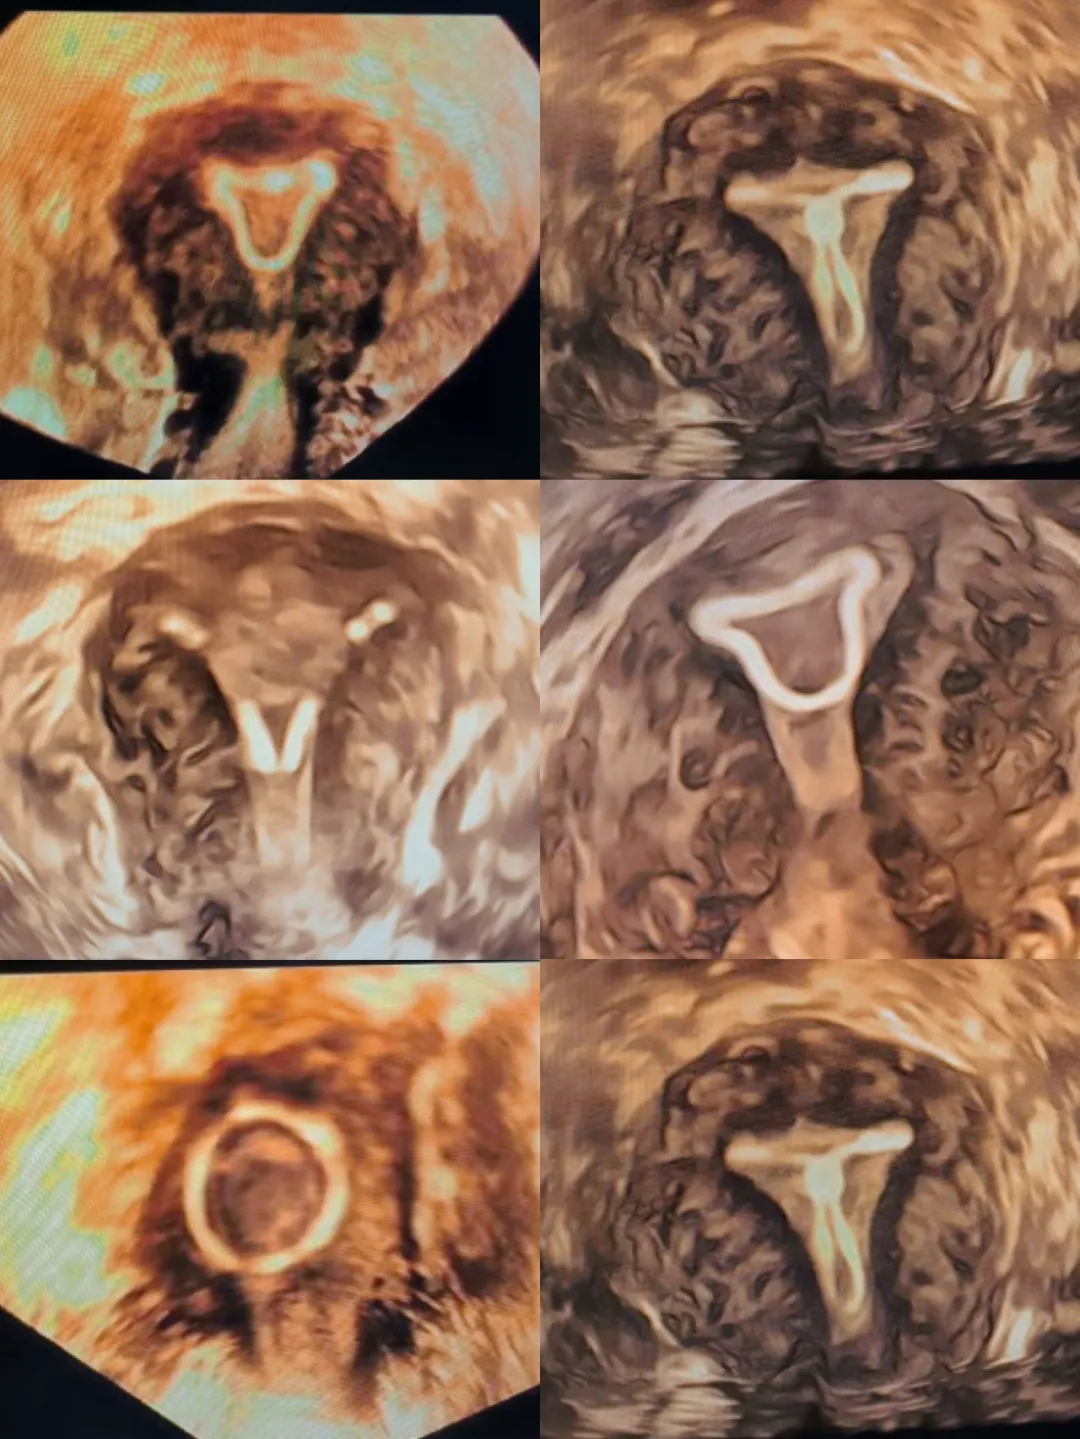

我院宫腔三维部分宫内节育器情况的判断

节育环检查情况